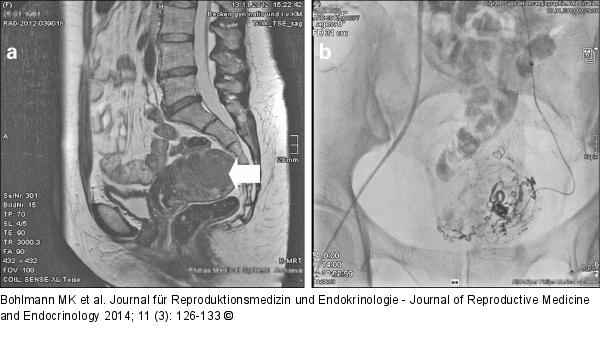

Abbildung 2a-b: Uterus myomatosus (a) Uterus myomatosus mit in der sagittalen MR-Darstellung nachweisbarem, intramuralem Fundus-/Hinterwand-Myom (Pfeil); (b) Digitale Subtraktionsangiographie der Embolisation mit Führungskatheter in der linken A. uterina (Cross-over-Technik) |

Abbildung 2a-b: Uterus myomatosus

(a) Uterus myomatosus mit in der sagittalen MR-Darstellung nachweisbarem, intramuralem Fundus-/Hinterwand-Myom (Pfeil); (b) Digitale Subtraktionsangiographie der Embolisation mit Führungskatheter in der linken A. uterina (Cross-over-Technik) |